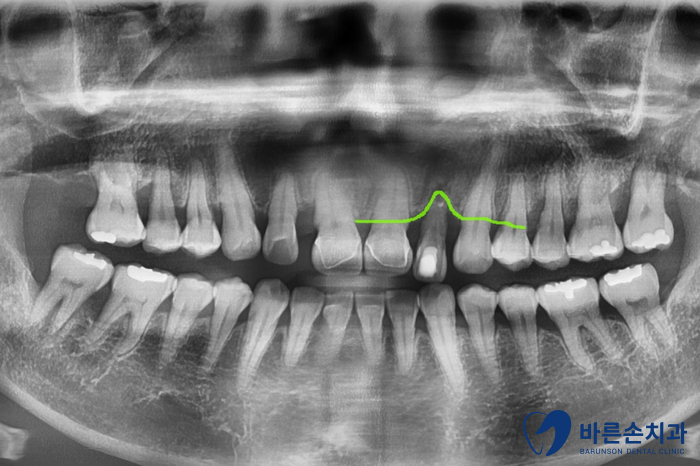

Before 25.05.08

보시면 앞니 하나가 유독 뼈가 내려가 있는 걸 볼 수 있어요.

치아를 잡아주는 뼈가 별로 없다보니

치아가 밑으로 내려오면서 많이 흔들리는 상태였습니다.ㅠㅠ